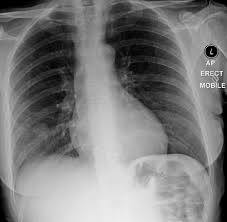

Pneumonia is an inflammation of the lungs and airways that causes breathing difficulties and deficiency of oxygen in the blood. Surgery to remove the portion of the lung containing the tumor is the recommended treatment in most cases. Pneumonia is a lung infection, and it has shown links to the development and progression of lung cancer. However, for the most part dog pneumonia and human pneumonia are caused by different bacterial strains and. An atypical acute respiratory distress syndrome working hypothesis published online ahead of print, 2020 apr 15.

Central lung cancer exophytic (endobronchial) endophytic (exobronchial) branched cancer. Tumors that cannot be operated on or those. Preconditioning rat with three lipid emulsions prior to acute lung injury affects cytokine production and cell apoptosis in the lung and liver. Pneumonia is an inflammation of the air sacs of the lungs. Primary lung cancer in dogs is relatively rare in dogs (under 1% of all cancer in dogs), but pulmonary pulmonary adenocarcinoma is cancer of the lungs, which can be primary (originates in the lungs) or secondary i took him to the vet and they diagnosed him with asphyxiation pneumonia. Being one of highly differentiated forms of lung cancer it is characterized by mostly peripheral localization and intraalveolar growth without significant destruction of respiratory tissue architectonics. Surgery to remove the portion of the lung containing the tumor is the recommended treatment in most cases. Cancerous cells can spread from various other parts of the dog's body to. A nationwide analysis in china. Who is most at risk of each? Pneumonia and lung cancer both affect the lungs, but while the former is easily treatable and the latter is oftentimes life threatening. Pneumonia is an inflammation of the lungs and airways that causes breathing difficulties and deficiency of oxygen in the blood. Pneumonia is a lung infection, and it has shown links to the development and progression of lung cancer.

How are they diagnosed and treated? Tuberculous pneumonia, although uncommon, is sometimes seen in dogs. If a person has lung cancer and gets pneumonia, the prognosis and life expectancy is poor. This is a malignant neoplasm, with the ability to grow rapidly and metastasize to distant parts of the body, including the organs, lymph nodes, bones, brain and eyes. How do dogs get pneumonia? Metastatic lung cancers (cancers that spread to the lungs from other locations) are much more common in dogs than primary lung cancers. Common symptoms include less activity and becoming tired more easily, a fever. Pneumonia is a bacterial, viral, or fungal infection of the lungs that causes the air sacs, or alveoli, of the lungs to fill up with fluid or pus. Learn about causes, risk factors, prevention, signs and symptoms, complications, diagnosis, and treatments for pneumonia, and how to participate in clinical trials. Efficacy of video assisted thoracoscopic lung biopsy: What are the overlapping symptoms and outlook? Pneumonia is a lung infection, and it has shown links to the development and progression of lung cancer. Types of lung carcinoma in dogs.

Pneumonia is an inflammation of the lungs and airways that causes breathing difficulties and deficiency of oxygen in the blood. Metastatic lung cancers (cancers that spread to the lungs from other locations) are much more common in dogs than primary lung cancers. Tumors that cannot be operated on or those. Being one of highly differentiated forms of lung cancer it is characterized by mostly peripheral localization and intraalveolar growth without significant destruction of respiratory tissue architectonics. Lung cancer usually occurs in older patients, is not breed specific and can be due to environmental factors.